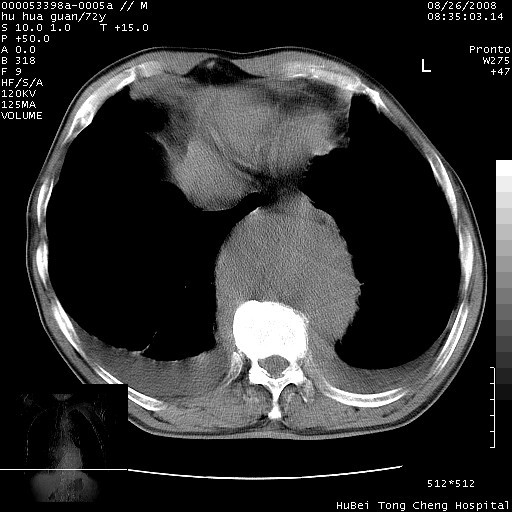

降主动脉前移位,后纵隔占位

后纵隔占位,降主动脉前移位;双侧胸腔积液;应排外食管病变侵犯血管可能;

可以明确的说。肯定不是主动脉夹层破裂出血!考虑为淋巴瘤或间叶组织来源的恶性肿瘤可能性大。右肺小结节建议薄层观察,如能发现恶性征象,那椎前改变就考虑为转移所致。至于双侧少量胸水乃静脉血回流受阻所致。

考虑胸主动脉下段夹层破裂。

考慮夾層動脈瘤破裂可能,建議增強掃描。

主动脉瘤破裂

建议排除结核引起的冷脓肿。